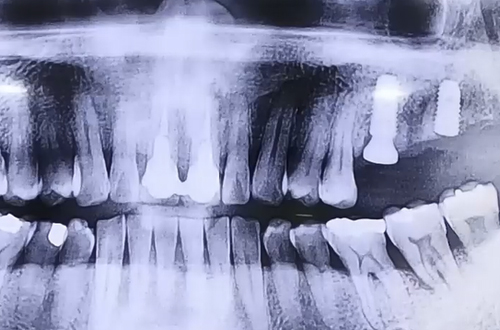

BEFORE

오른쪽 어금니의 불편함으로 내원해주셨던 환자분입니다.

검사를 해 보니 왼쪽 치아 상태가 눈으로도 흔들림이 보일만큼

많이 좋지 않았고, 그 탓에 오랫동안 오른쪽으로만 지속적으로

음식을 씹어 드시다 보니 오른쪽 치아도 안 좋아진 것이었는데요.

근본적인 원인이 왼쪽 위 어금니의 잇몸에 있었던 것입니다.

따라서 오른쪽은 잇몸 치료로 더 나빠지지 않도록 관리를 해 드리고

왼쪽으로 음식을 드실 수 있도록 왼쪽은 발치 후 임플란트를 계획했습니다.

왼쪽 위 어금니 두 개를 발치하게 되었는데,

하나는 잇몸 뼈의 상태가 괜찮아 즉시 식립으로 진행하였고

하나는 잇몸 뼈가 단단하지 않아서 염증을 깨끗이 치료하고 뼈이식을 한 뒤

기다렸다가 진행하는 지연 식립 임플란트로 진행한 사례입니다.